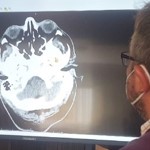

Fundamental para la orientación y el diagnóstico

Leer noticia completa